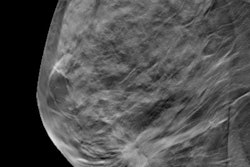

Digital breast tomosynthesis (DBT) found more than twice as many cancers as full-field digital mammography alone (FFDM) or a combination of the two technologies in a recent study, published online February 14 in the Journal of the American College of Radiology.

Digital mammography can miss up to 30% of breast cancers -- a statistic that has prompted the search for better breast cancer screening technology, the team noted. Previous studies comparing FFDM to DBT have shown that DBT increases cancer detection rates and reduces recalls, but these studies haven't necessarily examined the use of DBT alone.